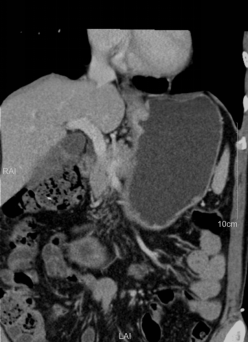

胃癌患者术前进行专科化、规范化的CT扫描;进行结构化诊断报告书写,术前影像学分期报告。

规范胃癌患者的CT扫描技术方案、诊断报告书写模式,提高胃癌术前分期诊断准确率,为临床制定治疗方案提供充分依据,与其他检查方法互补,实现个体化、精准医疗。